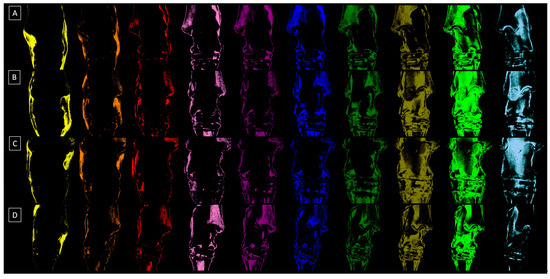

| Decomposition | S1 | S2 | S3 | S4 | S5 | S6 | S7 | S8 | S9 | S10 |

|---|---|---|---|---|---|---|---|---|---|---|

| Relative density (HU) | 1009 ± 163 | 1212 ± 111 | 1407 ± 98 | 1600 ± 134 | 1804 ± 112 | 2011 ± 99 | 2204 ± 107 | 2400 ± 133 | 2607 ± 129 | 2803 ± 147 |

| Color | Yellow | Orange | Red | Light purple | Dark purple | Dark blue | Dark green | Navy green | Light green | Light blue |

| HEX code | #FFFF00 | #E08000 | #FF0000 | #E080C0 | #800080 | #0000FF | #008000 | #808000 | #00FF00 | #A6CAF0 |